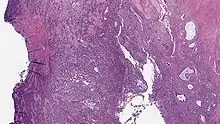

| Micrograph of a low-grade endometrial stromal sarcoma. H&E stain. | |

Low-grade endometrial stromal sarcoma consists of cells resembling normal proliferative phase endometrium, but with infiltration or vascular invasion. These behave less[3] aggressively, sometimes metastasizing, with cancer stage the best predictor of survival. The cells express estrogen/progesterone-receptors.

Microscopy

- Monotonous ovoid cells to spindly cells with minimal cytoplasm.

- Prominent arterioles. Angiolymphatic invasion common.

- Up to 10-15 mitotic figures per 10 HPF in most active areas.

- Tongue-like infiltration between muscle bundles of myometrium.

- May exhibit myxoid, epithelioid and fibrous change.

- May have foam cells or hyalinization in the stroma.